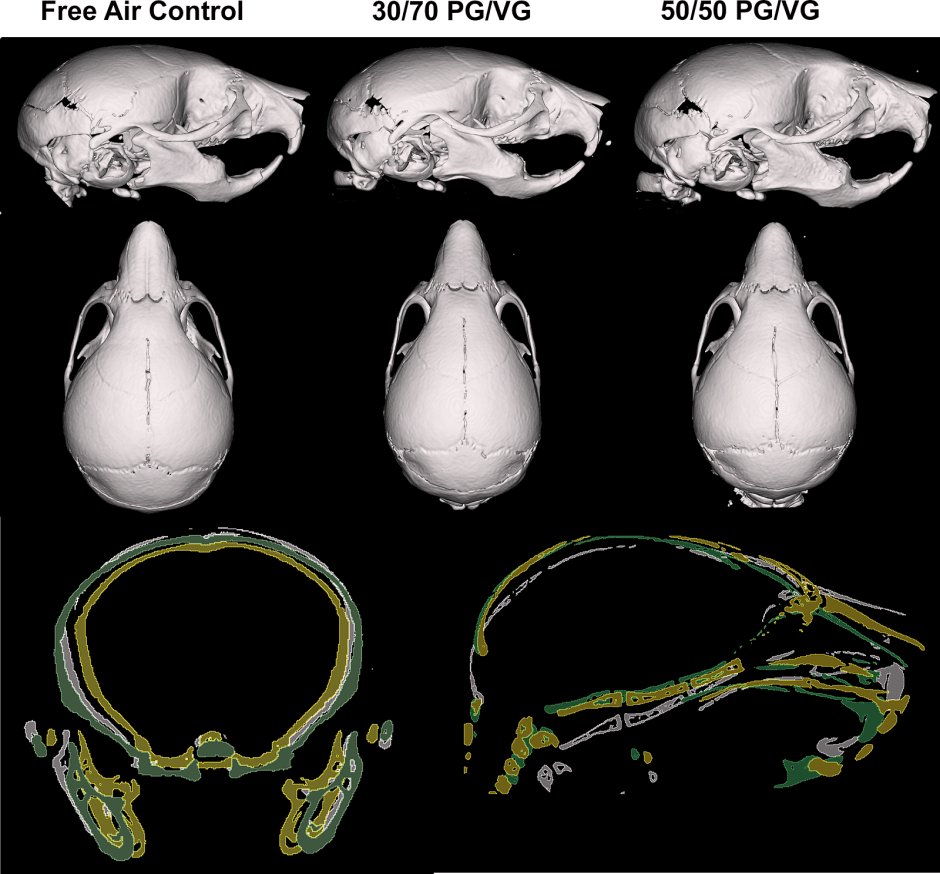

В эксперименте, который провела команда из Университета штата Огайо под руководством профессора анатомии Джеймса Крэя, беременным мышам в течение беременности ежедневно по четыре часа давали вдыхать пары безникотиновых жидкостей с разным соотношением пропиленгликоля (PG) и растительного глицерина (VG) — 30/70 и 50/50. Контрольная группа дышала чистым воздухом.

После рождения потомство провело с матерями 14 дней, затем мышат подвергли эвтаназии, изучив их тела и черепа с помощью микротомографии. Ученые обнаружили, что детеныши из группы с меньшей концентрацией пропиленгликоля (PG/VG 30/70) отличались укороченными черепами и более узкими мордами по сравнению с контрольной группой. Кроме того, у них была сниженная масса тела.

В группе PG/VG 50/50 статистически значимых отличий от контрольной группы не выявили. Однако авторы подчеркивают: даже смеси без никотина и с пониженным содержанием PG нельзя считать безопасными — особенно для беременных.

изменения в черепах мышей при научном эскперименте